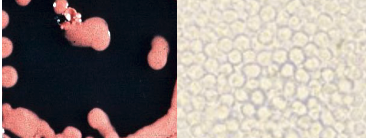

C.albicans

C.Glabrata

C.tropicalis

C. parapsilosis

C.Krusei

Cryptococcus neoformans

Tricosporen

Geotrichum

malassezia furfur

Rhodotorula

Saccharomyces

prototheca